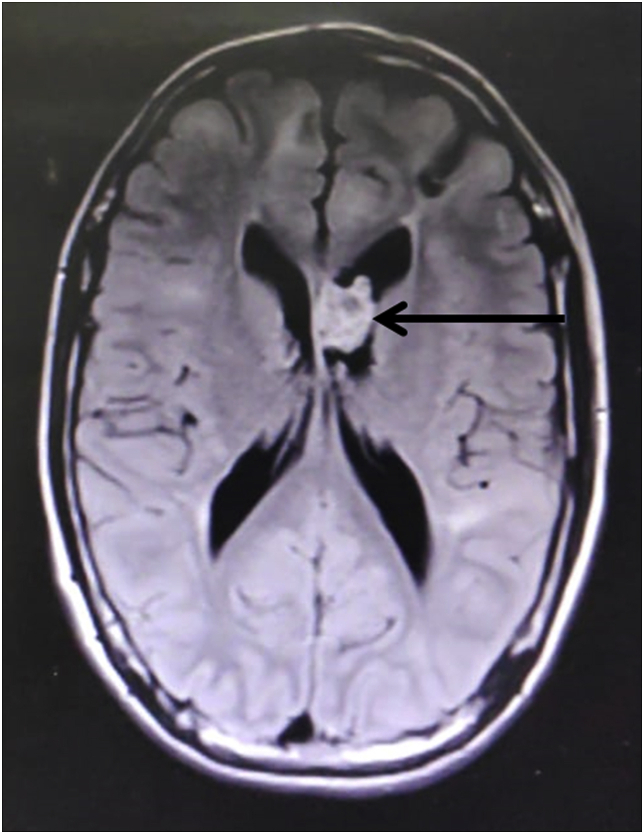

Laboratory examination revealed normal hemogram, liver function, renal function, and serum electrolyte. Non-contrast computed tomography (NCCT) scan of the brain showed multiple calcified subcortical nodules (yellow arrowhead, Fig. 2) and left lateral ventricle lesion (black arrowhead, Fig. 2). For a better characterization of the lesion, the MRI brain was done, which revealed a heterogenous contrast-enhancing lesion in the left lateral ventricle. The lesion was hypointense on T1, T2 sequences, and hyperintense on FLAIR sequences, suggestive of giant cell astrocytoma (Fig. 3).

Fig. 3.

MRI brain showed a heterogeneous contrast enhancing lesion in the left lateral ventricle, hyperintense on FLAIR sequences suggestive of giant cell astrocytoma.